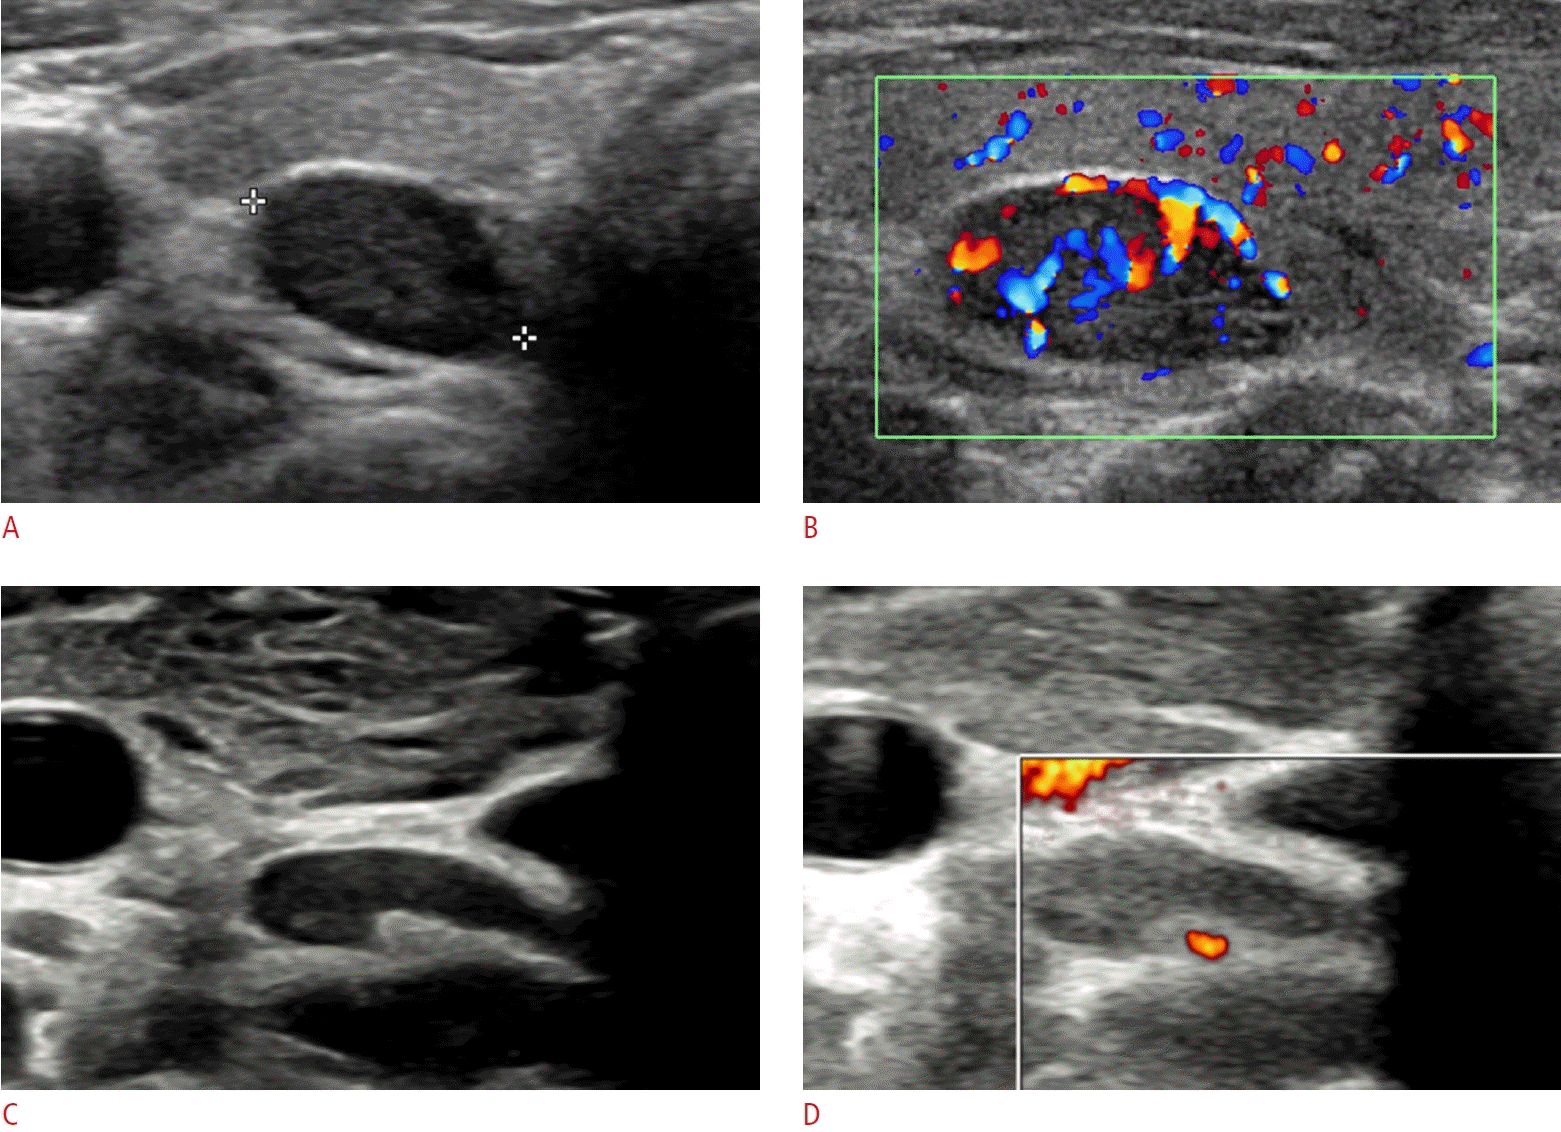

40. Reeder SB, Desser TS, Weigel RJ, Jeffrey RB. Sonography in primary hyperparathyroidism: review with emphasis on scanning technique. J Ultrasound Med. 2002; 21:539–552.

41. Johnson NA, Tublin ME, Ogilvie JB. Parathyroid imaging: technique and role in the preoperative evaluation of primary hyperparathyroidism. AJR Am J Roentgenol. 2007; 188:1706–1715.

42. Chandramohan A, Sathyakumar K, John RA, Manipadam MT, Abraham D, Paul TV, et al. Atypical ultrasound features of parathyroid tumours may bear a relationship to their clinical and biochemical presentation. Insights Imaging. 2014; 5:103–111.

43. Wolf RJ, Cronan JJ, Monchik JM. Color Doppler sonography: an adjunctive technique in assessment of parathyroid adenomas. J Ultrasound Med. 1994; 13:303–308.

44. Huppert BJ, Reading CC. Parathyroid sonography: imaging and intervention. J Clin Ultrasound. 2007; 35:144–155.

47. Centello R, Sesti F, Feola T, Sada V, Pandozzi C, Di Serafino M, et al. The dark side of ultrasound imaging in parathyroid disease. J Clin Med. 2023; 12:2487.

49. Hara H, Igarashi A, Yano Y, Yashiro T, Ueno E, Aiyoshi Y, et al. Ultrasonographic features of parathyroid carcinoma. Endocr J. 2001; 48:213–217.

50. Liu J, Zhan WW, Zhou JQ, Zhou W. Role of ultrasound in the differentiation of parathyroid carcinoma and benign parathyroid lesions. Clin Radiol. 2020; 75:179–184.